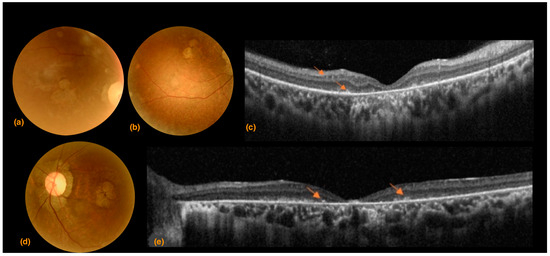

3.2. Case 2